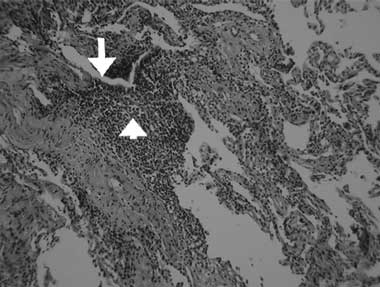

A computed tomography (CT) scan of the chest showed inhomogeneous opacities, as well as dilated airways crowded in the medial segment of the right middle lobe and inferior segment of the lingula, without mediastinal lymphadenopathy (Box, B). A fibrobronchoscopic examination to verify central bronchial patency showed no intraluminal obstruction in the affected bronchi. Cultures of the lavaged bronchial fluid were negative for tuberculosis and other microorganisms, and no malignant cells were found in aspirated specimens. A transbronchial biopsy from the atelectatic middle lobe revealed lymphocytic bronchiolitis with a moderate degree of mononuclear cell infiltration, predominantly by lymphocytes, in the terminal bronchiolar walls and adjacent interstitial areas, and no granuloma formation (Box, C).